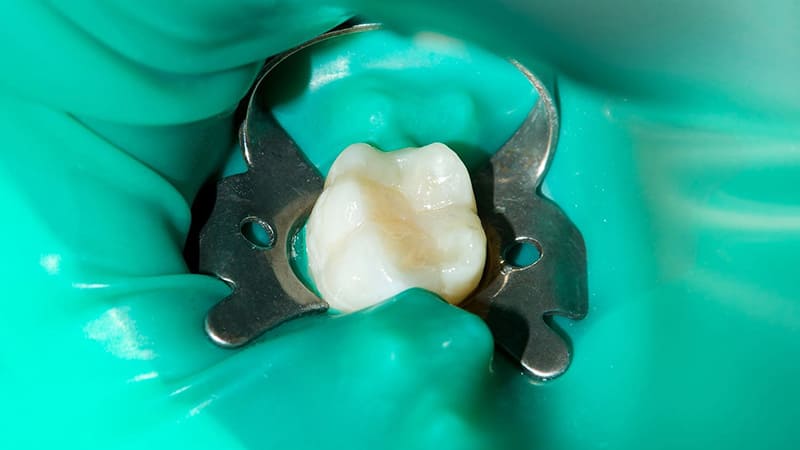

ラバーダム防湿

根管治療する歯だけをゴムのシートで隔離し、唾液や細菌が入り込まないようにする方法です。根管内を清潔に保ち、再感染のリスク軽減にもつながります。

治療環境の確保

処置中の感染を防ぐため、ラバーダム防湿を行います。また、必要に応じて電動麻酔器を使用した麻酔を行い、痛みに配慮しながら根管治療を進めます。